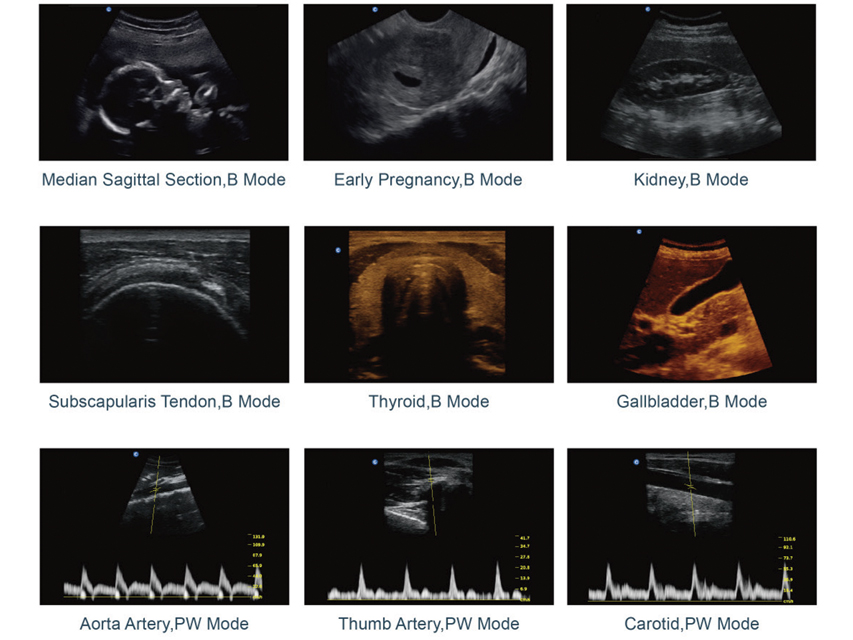

CHISON ECO2 ar 1 zondes savienotāju, bez zondes.ECO2. Jaudīga un pieejama melnbalta sistēma.- Īpaši kompakts un īpaši viegls svars, viegli pārnēsājams.- Jaunākā LED ekrāna tehnoloģija, īpaši spilgti attēli ļauj ērti apskatīt skenēšanu pat ārpus telpām.- Ergonomisks monitora dizains, 30 grādu rotācija, regulējams.- Īpaši ilgs akumulatora darbības laiks līdz 2,5 stundām, skenēšanai ārpus telpām.- Ar vienu taustiņu, lai palielinātu attēlu līdz pilnam ekrānam, viegli skatāms no attāluma.- Racionalizēta darbplūsma, viegli lietojama, 6 viena taustiņa diagnozes cikla pabeigšanai.Displeja režīmi un attēlu apstrāde.B, B/B, 4B, M, B/M, PW (tikai ECO2, ECO3EXP.) vairāku frekvenču attēlveidošana.Attēlveidošanas apstrāde.- Saliktā attēlveidošana - trapecveida.- i-image viedā attēla optimizācija - automātiska PW izsekošana.- THI (audu harmoniskā attēlveidošana) (tikai ECO2, ECO3EXP.).- SRA (plankumu samazināšanas algoritms) - Chroma.- Pilna digitālā stara veidotājs - AIO (automātiska pilnekrāna displeja attēla optimizācija).Lietotāja interfeiss.- Salokāms vadības panelis un burtciparu tastatūra.- Aizmugurgaismota tastatūra, kas nodrošina labu redzamību tumšā telpā.- Indikatora gaismas identificē aktivizētos taustiņus.- 8 TGC slaidi ērtai regulēšanai.- Saīsinātā poga ātrai regulēšanai (lietotāja definēts karstais taustiņš).- Veikls un skaidrs tastatūras izkārtojums, ārsts var viegli atcerēties.- Interaktīvs fona apgaismojums - lietotāja definēts priekšiestatījums.Racionalizēta darbplūsma, viena atslēga, lai.- Atlasiet vajadzīgo lietojumprogrammu ar automātisko sākotnējo iestatījumu.- Optimizēt attēlu automātiski (AIO) - izveidot ziņojumu.- Saglabāt nekustīgu attēlu un CINE cilpu - mērīt.- Drukājiet ar datora printeri* (lāzeru vai tintes printeri) vai video printeri.*Skatiet saderīgo printeru sarakstu mūsu vietnēs.EASYVIEW™ arhīvu sistēma.- Attēlu arhīvs cietajā diskā un USB mobilajā atmiņā.- Vairāki attēlu formāti: BMP, JPG, DCM, CIN, AVI.- Kino apskate: automātiska, manuāla (var iestatīt automātiskās pārskatīšanas segmentu) 2D, M, PW (tikai ECO2, ECO3EXP.) attēliem.- Kino atmiņas ietilpība (256 kadri/10 s).- 3 USB porti.Normas.IEC 60601-1, IEC 60601-1-1 Elektriskā medicīniskā iekārta, IEC 60601-1-2 elektromagnētiskā saderība, IEC 60601-1-4 Programmējamās medicīnas sistēmas, IEC 60601-2-37.Tehniskās specifikācijas.Izmēri un svars: 33,5x15,5xh 35 cm (13,2x6,1xh 13,8), 6 kg.Displejs: 12 LED, augsta izšķirtspēja 1024x768.Jauda: AC 100-240 V - 50/60 Hz.Uzlādējams litija jonu akumulators - opcija.- Programmatūra (valodu var pārslēgt lietotājs): GB, IT, FR, ES, DE, CZ, TR, CN, RU.- Lietotāja rokasgrāmata: GB, IT, CN.Standarta piederumi.- 12” augstas izšķirtspējas LED monitors - melnbalts.- 12” augstas izšķirtspējas LED monitors - krāsains.- 8G atmiņas karte.- Karstā atslē